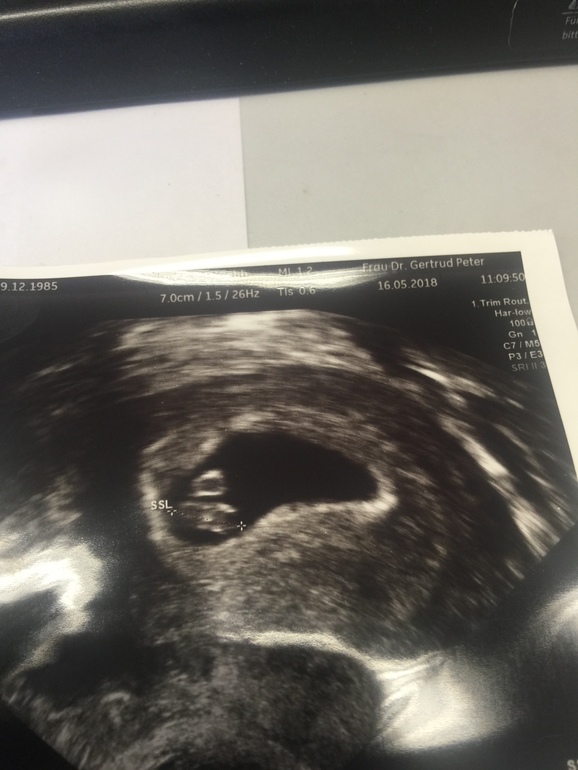

Познакомилась с нашим вторым чудом! 7+2 нед.

УЗИ, КТГ, доплерУрааа... нашли мое чудо! И все как в первый раз. Такие эмоции, я весь день на эмоциях и даже штраф за парковку мне не смог испортить настроение. Все с нашим ляликом хорошо, сердечко бьется, размер 1,08 см. ПДР поставили на 30.12., вот и будет нам Новый Год! Мы тааак рады!!!!!

16.05.2018